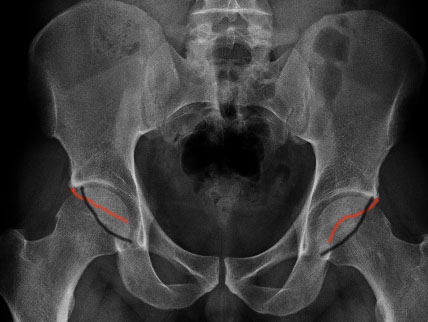

Xray diagnosis

1. Crossover sign - crossover of the anterior and posterior acetabular wall

Crossover sign - anterior wall in red, posterior wall in black